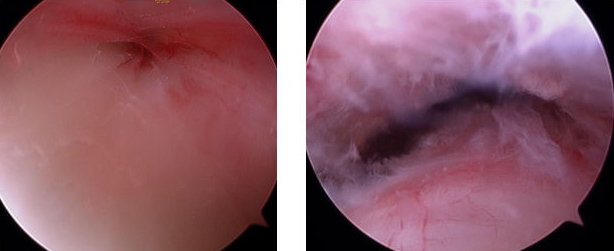

Intraoperatives Bild einer Sehnenscheidenreizung der Achillessehne vor der operativen Sanierung (links) und nachher (rechts)